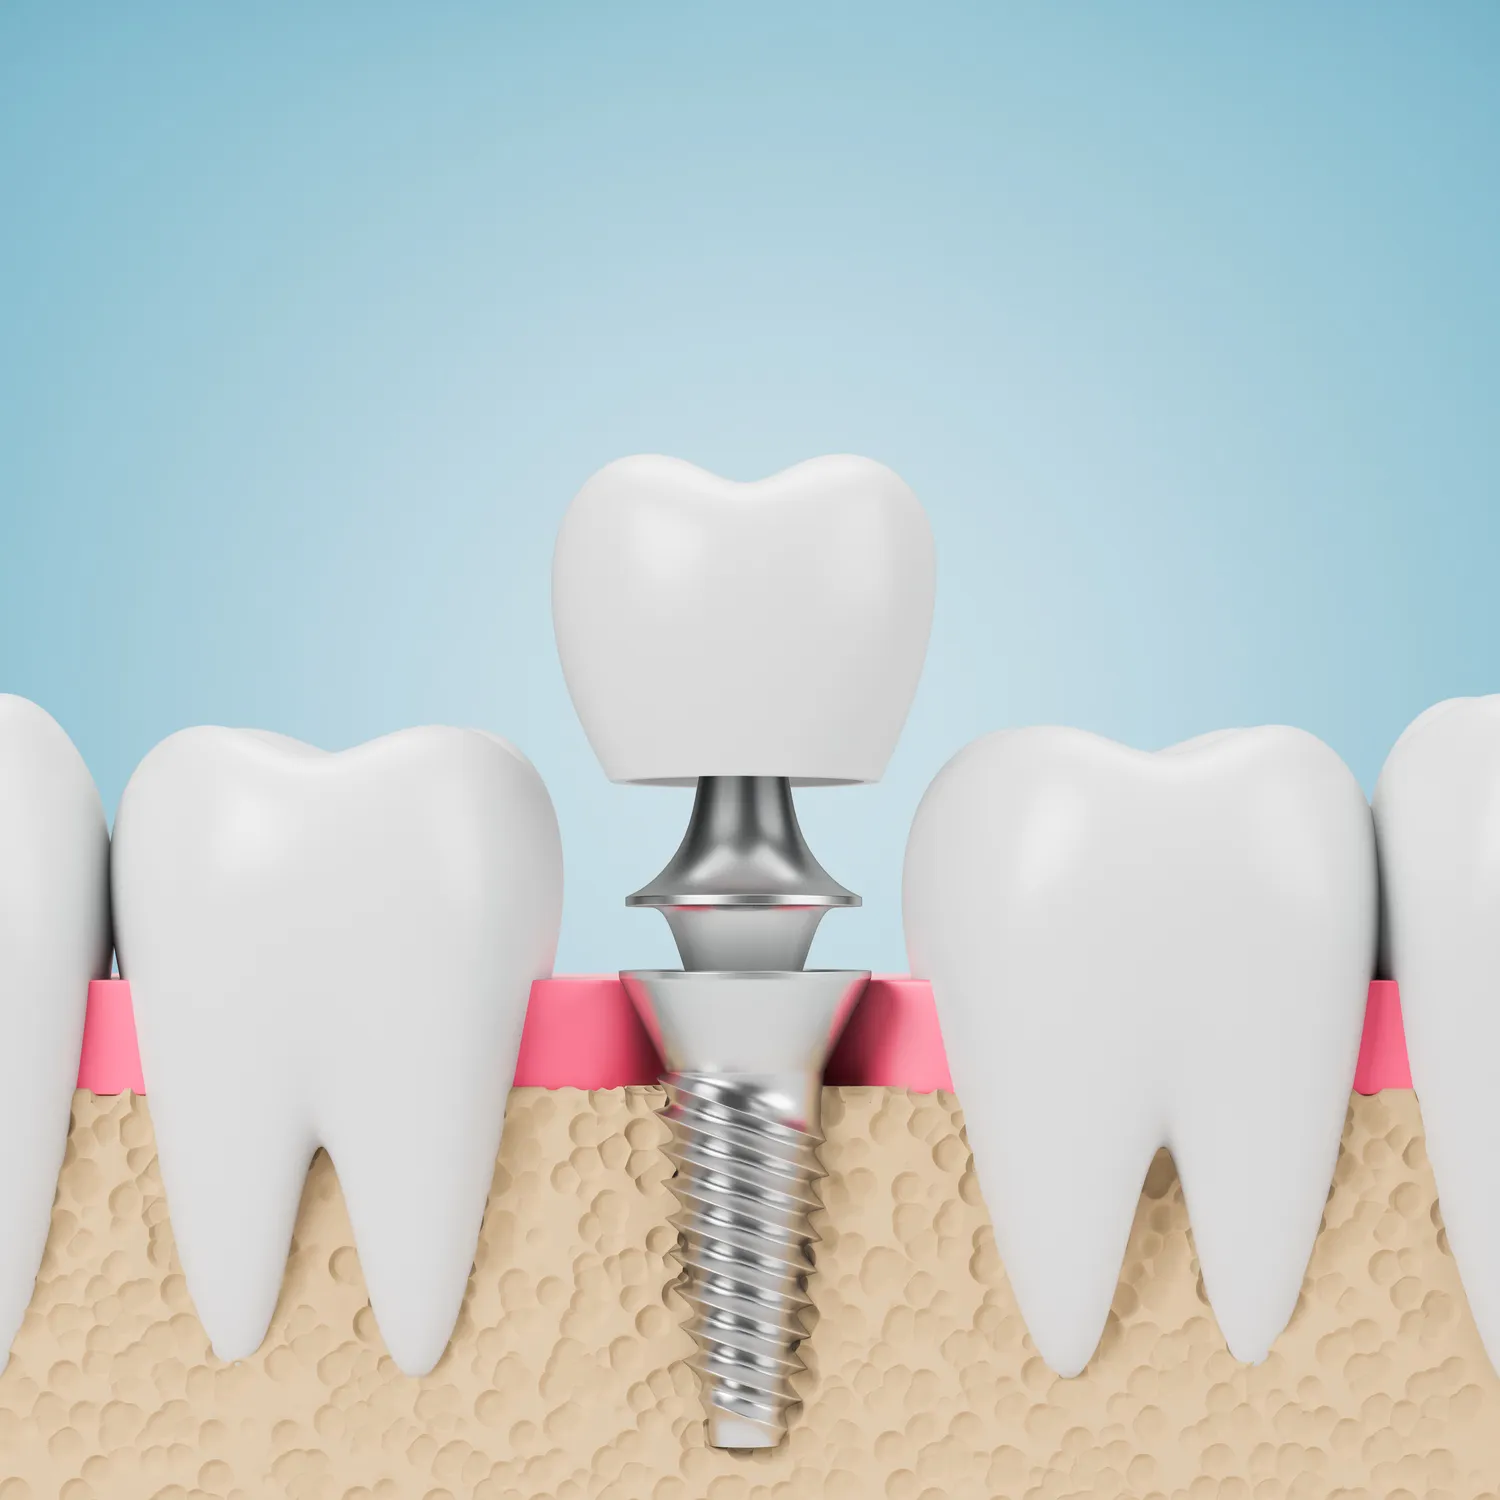

Jakie są etapy procesu wszczepienia implantów zębów

Proces wszczepienia implantów zębów składa się z kilku kluczowych etapów, które wymagają staranności i precyzji ze strony specjalisty. Pierwszym krokiem jest dokładna diagnostyka, która obejmuje badania obrazowe, takie jak tomografia komputerowa, oraz szczegółowy wywiad medyczny. Na tym etapie lekarz ocenia stan zdrowia pacjenta oraz jakość tkanki kostnej, co pozwala na podjęcie decyzji o dalszych krokach. Następnie, jeśli pacjent kwalifikuje się do zabiegu, przeprowadza się procedurę wszczepienia implantu. W trakcie tego etapu chirurg wykonuje niewielkie nacięcie w dziąśle i umieszcza implant w kości szczęki lub żuchwy. Po zakończeniu zabiegu pacjent otrzymuje zalecenia dotyczące pielęgnacji rany oraz ewentualnych leków przeciwbólowych. Kolejnym kluczowym etapem jest proces osteointegracji, który trwa od kilku tygodni do kilku miesięcy. W tym czasie implant łączy się z kością, co jest niezbędne dla jego stabilności. Po zakończeniu osteointegracji następuje etap mocowania korony protetycznej, która jest indywidualnie dopasowana do kształtu i koloru pozostałych zębów pacjenta.